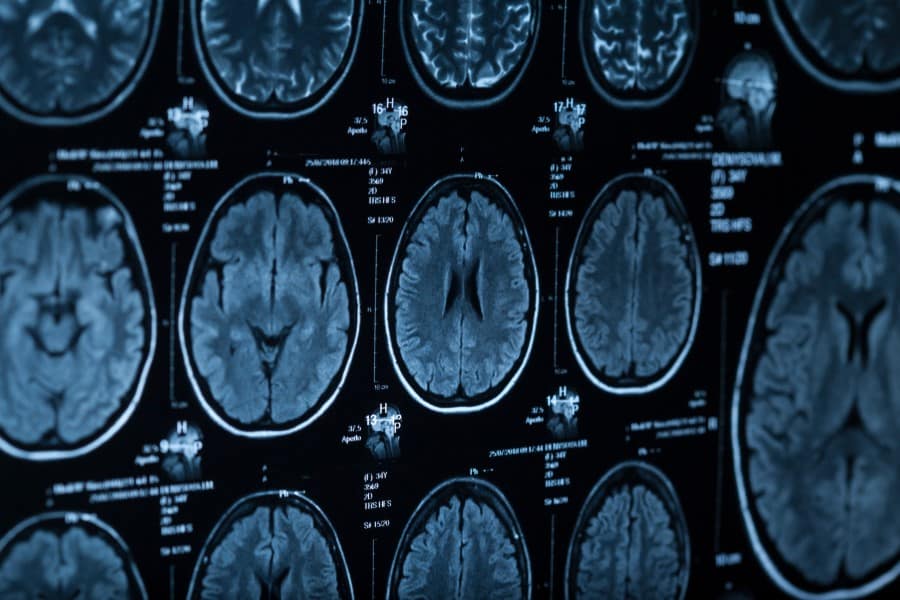

Tomografia głowy - na czym polega? Wskazania i przeciwwskazania, przygotowanie do badania

Tomografia komputerowa (TK) jest elementem diagnostyki obrazowej w ocenie zakresu potencjalnych zmian w obrębie mózgowia, zatok oraz ucha środkowego i wewnętrznego. Pojawienie się objawów takich jak nagła utrata przytomności, omdlenia czy niedowład może wskazywać na konieczność przeprowadzenia tomografii komputerowej głowy. Jak przebiega procedura przeprowadzania tomografii komputerowej głowy? Jak przygotować się do badania? Kiedy TK jest zalecana? Jakie są przeciwwskazania do tego badania?

Jak wygląda tomografia komputerowa głowy?

Przed samym wykonaniem badania należy zdjąć wszelkiego rodzaju metalowe elementy np. biżuterię, protezy zębowe i aparaty słuchowe. Jeśli jest to badanie z kontrastem, będzie on podawany dożylnie, przez wenflon. Po wejściu do pomieszczenia pacjent kładzie się na specjalnie wysuwanym stoliku, który będzie przesuwał się w kierunku aparatu, aby odpowiednio usytuować chorego. Po zakończonym badaniu warto pamiętać o wypiciu 1,5-2 litrów wody niegazowanej, aby nie obciążać nerek i jak najszybciej pozbyć się kontrastu z organizmu.